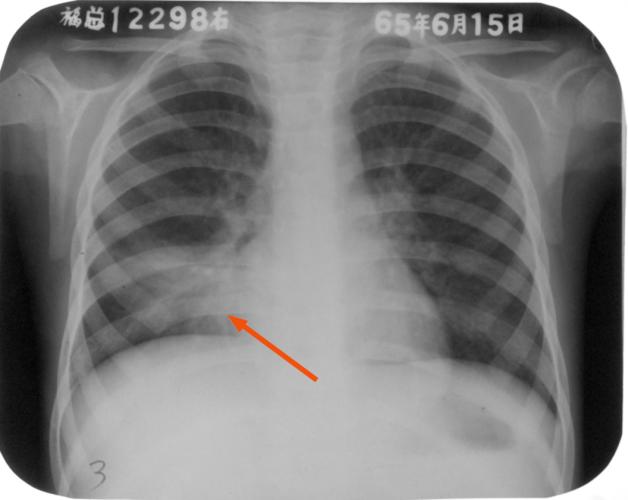

肺部图片胸片,胸片图片肺大泡

胸片如何看炎症马上把这批病例刻在脑海里

胸片图片肺大泡

胸片图片

肺结核胸片

肺炎胸片